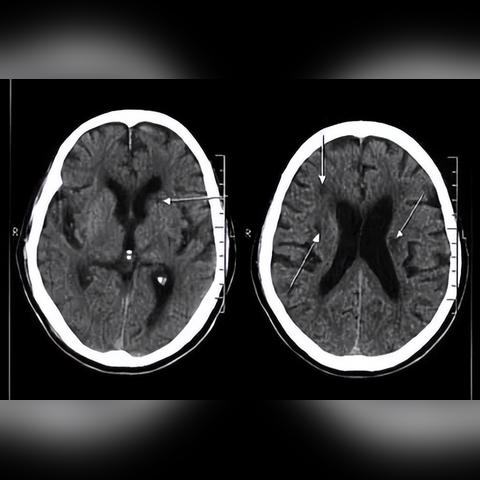

腦梗是由于腦部血管阻塞導致血液供應不足,使局部腦組織發(fā)生缺血、壞死的一種疾病,主要癥狀包括突發(fā)性的肢體無力、言語不清、視覺障礙等,傳統(tǒng)的治療方法主要包括藥物治療、手術治療和康復治療等,隨著醫(yī)學技術的不斷進步,治療腦梗的方法也在不斷更新。